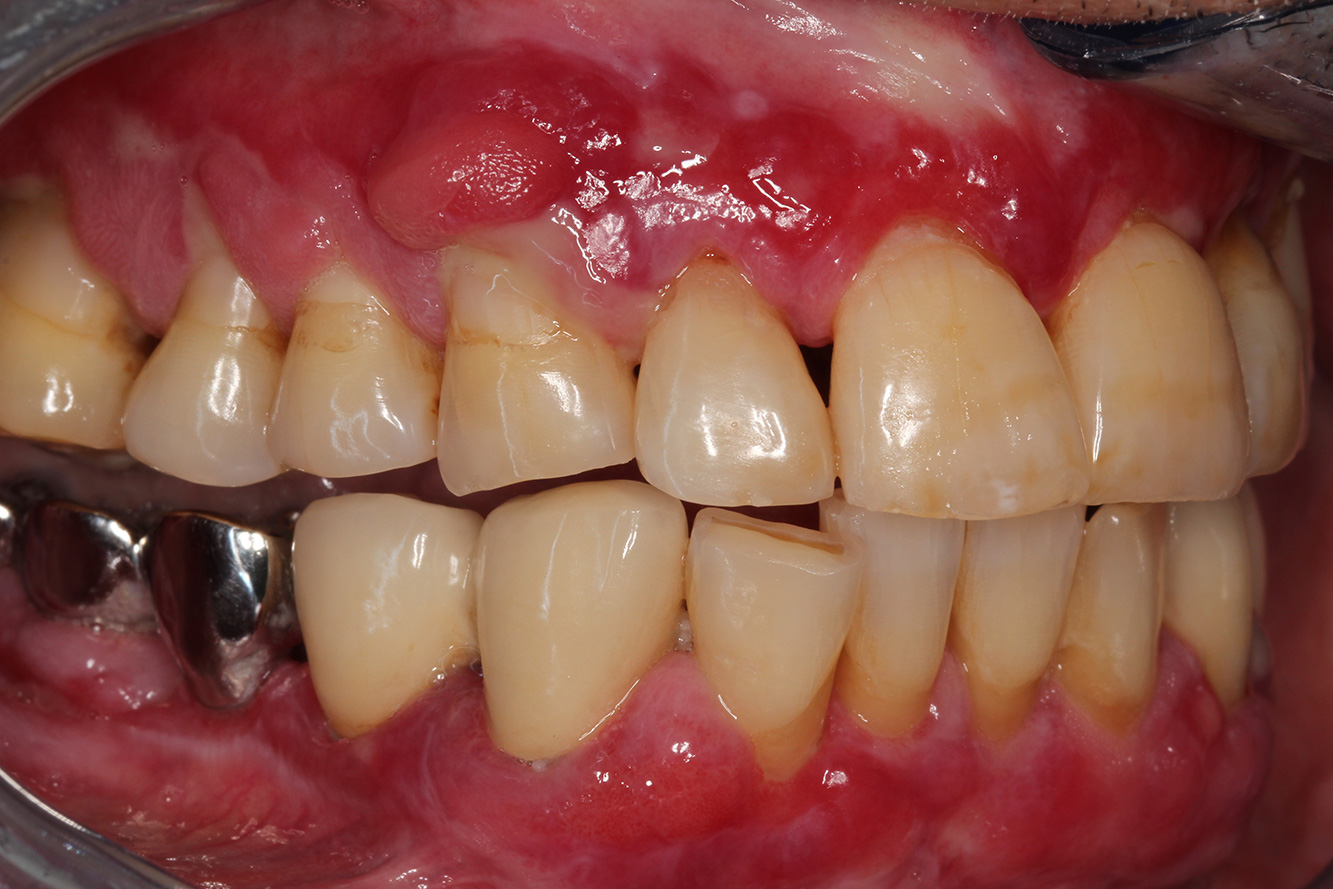

Ein 71-jähriger Patient mit Z.n. Nierentransplantation und Hypertonie (Bluthochdruck) stellt sich vor. Bedingt durch die Krankengeschichte ist eine Dauermedikation mit Cyclosporin, zur Unterdrückung der Immunabwehr, und Amlodipin, zur Blutdrucksenkung, erforderlich. Außerdem berichtet der Patient über empfindliches Zahnfleisch und Zahnfleischbluten. Aus mundgesundheitlicher Sicht zeigt sich ein saniertes Gebiss mit acht fehlenden Zähnen, ausgeprägte Gingivawucherungen, eine Parodontitis Stadium II, Grad B mit aktiven Taschen und eine initiale Wurzelkaries an Zahn 22. In der Kariesrisikoabschätzung wird ein mittleres Kariesrisiko (API 60) festgestellt. Für die Prophylaxesitzung lassen sich folgende Behandlungsempfehlungen ableiten.

Anhand der Krankengeschichte lässt sich ein besonderes Komplikationsrisiko erkennen. Aufgrund des Nierentransplantats ist der Patient immunsupprimiert (Cyclosporin), verfügt also über ein geschwächtes Immunsystem und benötigt eine Infektionsprophylaxe (Empfehlung: 2 g Amoxicillin als Antibiotikum 1h vor Sitzung). Gleichzeitig birgt die Dauermedikation des Patienten ein erhöhtes Erkrankungsrisiko, da die festgestellten Gingivawucherungen medikamentenassoziiert sind (21).

Besonders im Bereich der Motivation und Instruktion muss auf die Situation des Patienten eingegangen werden. Durch die Gingivawucherungen gestaltet sich die häusliche Mundhygiene schwierig. Die erhöhte Anfälligkeit für Infektionen sowie das Fortschreiten und die Neuentstehung der Wucherungen (22) sollte auf Augenhöhe thematisiert werden. Gleichzeitig müssen die individuell auf den Bedarf abgestimmten Hygienetechniken vermittelt werden.